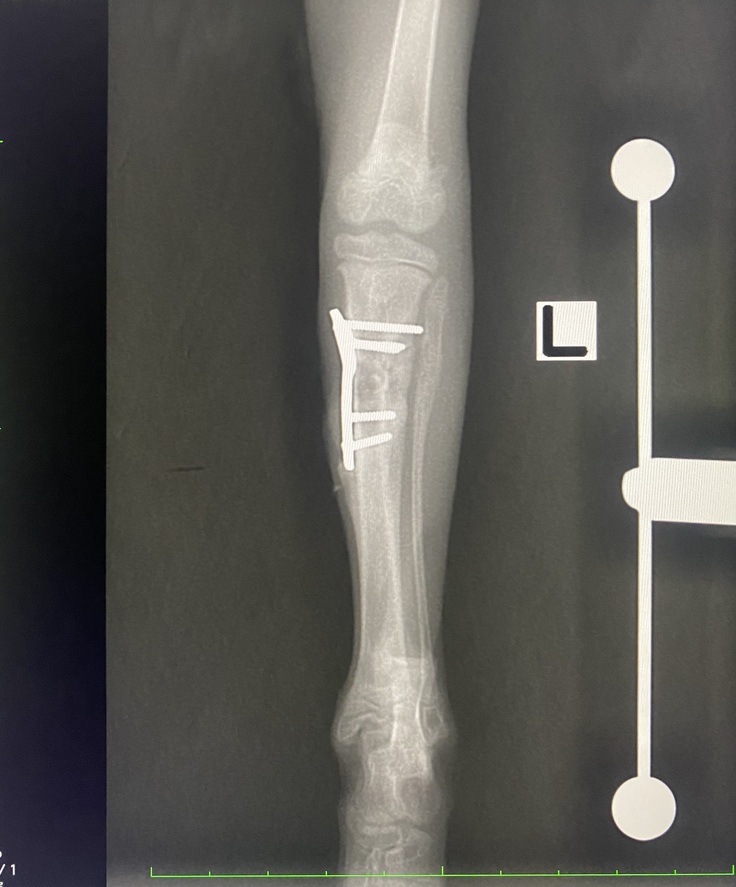

【左足 術後】

【本日】骨が太く隙間なく癒合しています。腓骨(細い方)も太く真っ直ぐになりました。

経過は良好で次回上腕もしっかり癒合していれば、プレートを外す手術になります。